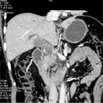

Measurements

在横断位.冠状位.矢状位上分别测量Pancreatic Ca的最大径线及Pancreatic Ca的体积测量

Axial Dmax= 40.7 mm

Coronal Dmax= 37.2 mm

Sagittal Dmax= 35.8 mm

体积:23.694 cm³